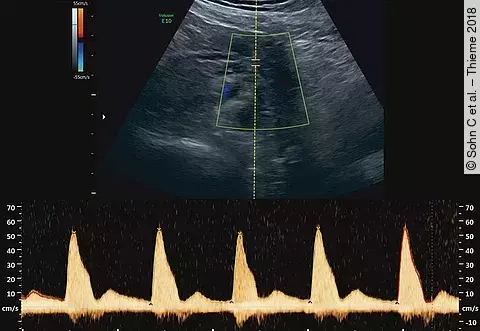

Doppler-Quiz26-jährige II.-Gravida I.-Para bei 21 + 6 SSW

Vorgeschichte: Z. n. Sectio bei 25 + 0 SSW bei schwerer Plazentainsuffizienz in der letzten Schwangerschaft. Die Patientin nahm aufgrund der Plazentainsuffizienz in der letzten Schwangerschaft Aspirin 100 1 × tgl. ein. Die Thrombophilie-Abklärung sei unauffällig gewesen.